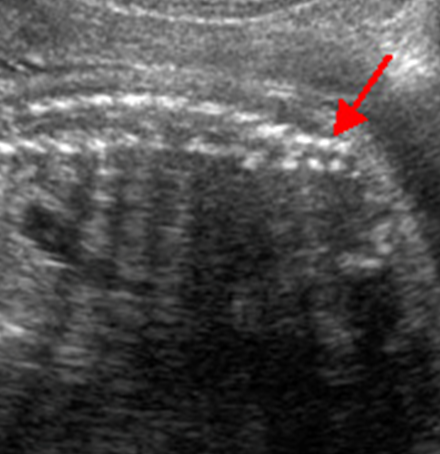

IPKD (ARPKD)